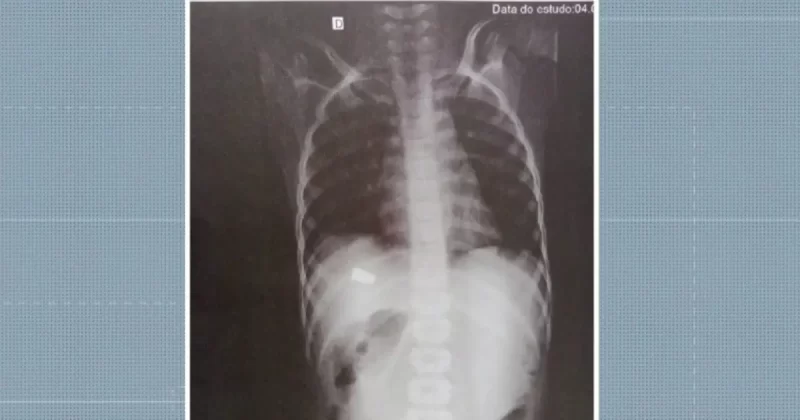

Uma imagem do raio-x do garoto mostra a região onde a vítima foi atingida pela bala. A autoria do disparo está sendo apurada pela polícia. As guias periciais foram expedidas para o entendimento do caso.